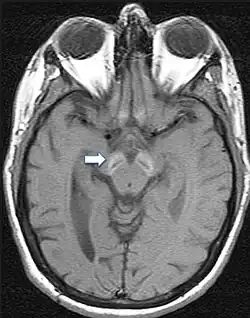

Da die Symptome meist unspezifisch sind, ist eine gesicherte Diagnose nur über bildgebende Verfahren und genetische Sequenzierung möglich. Im fortgeschrittenen Stadium sind mittels Magnetresonanztomographie Veränderungen in der Substantia nigra sowie im Globus pallidus erkennbar, die durch die Anlagerung von Eisen entstehen.[9][25] Frühe Anzeichen vor dem Auftreten von nachweisbaren Eisenablagerungen könnten ein Anschwellen der Substantia nigra sowie eine Hyperintensität in einer T2-gewichteten MRT-Aufnahme des Nucleus dentatus sein.[26] Letztendlich kann die Diagnose jedoch nur durch die Identifizierung der Mutation des WDR45-Gens abgesichert werden. Zur Diagnose der häufig auftretenden Epilepsie sind EEGs angezeigt.